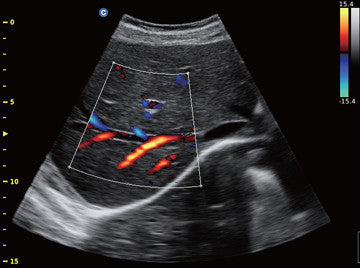

Continuous Wave Doppler (CW)--Detect blood flow with high velocity and help doctors diagnose with more clinical information.

Triplex--combines B, Color, with PW to help the user make accurate diagnosis thus improving the efficiency.